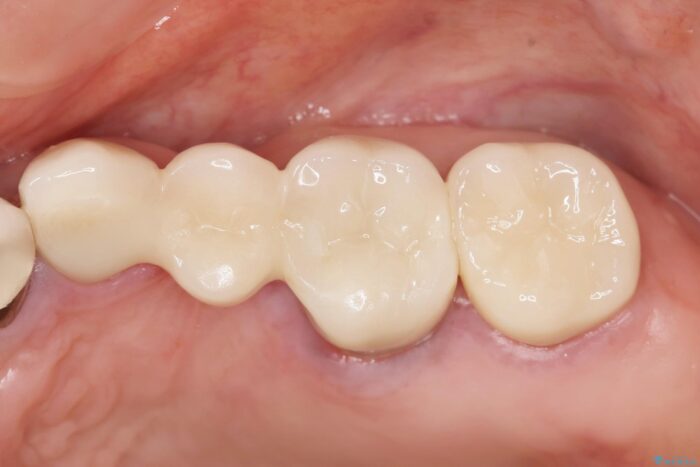

治療後について

ブリッジに審美的でないイメージやあまり良くないイメージをお持ちの方を多々お見受けしますが、適切な設計とすることで、見た目に自然で審美的なブリッジ治療を行うことができます。